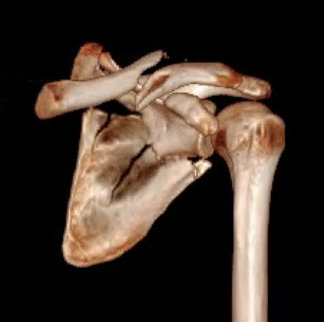

Scapular neck fracture with clavicle fracture